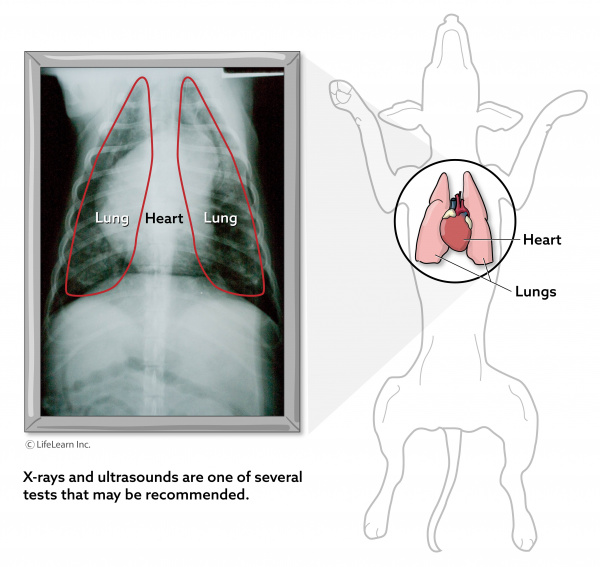

Dog Lung Cancer Xray - Goldenacresdogs.com from animalpetdoctor.homestead.com Melanoma, hemangiosarcoma, mast cell tumor and osteosarcoma can all cause labored breathing and coughing with metastasis. Similar to other cancers in dogs, it is seen more often in dogs over seven years of age. What causes this type of cancer? Any breed can be affected by this type of cancer, but boxers have been found to be more more at risk of developing adenocarcinoma of the lungs than other breeds. The most common extranodal lymphoma affects the. The two most common types in dogs are caused by epithelial lung tumors and primary lung tumors. The second type is metastatic lung cancer whichis cancer that originates elsewhere in the body such as a leg bone, the mouth, or the thyroid gland, but has spread to the lung via the bloodstream. Additionally, there are a number of chemicals used in landscaping and agriculture such as pesticides, herbicides, and insecticides that contain carcinogens that are linked to cancer.